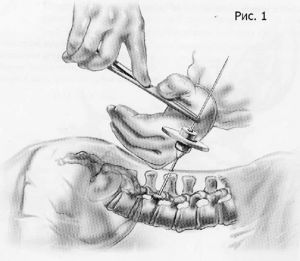

Хирургическое лечение спондилолистеза заключается в фиксации «разболтанных» позвонков титановыми винтами. Винты вводятся в позвонки через дужки позвонков (с лат. «педикули»), поэтому такая фиксация называется «транспедикулярной». Данный метод фиксации позвонков был впервые применен Roy-Camille в 1963г. и используется благодаря своей высокой эффективности по всему миру до настоящих дней.

Наиболее современным методом фиксации в настоящий момент является миниинвазивная технология введения винтов через небольшие разрезы. Этот метод позволяет меньше травмировать мышцы разгибатели позвоночника при введении винтов, а также более быстрому выздоровлению пациента и возвращению к обычному образу жизни, активному отдыху и работе. Технология данной фиксации заключается в использовании канюлированных винтов, т.е. винтов с отверстием в центре. В начале в тело позвонка вводится спица, а уже по спице вводится винт. Удаление грыжи диска и введение кейджа в межтеловой промежуток производится через тот же разрез, что и введение винтов.